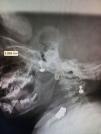

En la radiografía lateral de columna cervical se midió el espacio preodontoideo, siendo de 3.998mm, que aunado a la clínica fue indicativo de afectación de la columna cervical con una subluxación atlantoaxoidea (fig. 3).

Al mes de tratamiento, presentó una evolución clínica y analíticamente favorable, con disminución del diámetro de ambas rodillas, mejoría de fuerza muscular en miembros inferiores y deambulando sin apoyo. Los arcos de movilidad de cabeza y cuello eran completos y sin limitación. Los reflejos osteotendinosos patelares se encontraban normales y el reflejo cutáneo-plantar con respuesta flexora bilateral. La exploración oftalmológica fue normal. Las transaminasas disminuyeron (AST 93 U/l, ALT 58 U/l), igual que la IgG (1.075 mg/dl). La tomografía computarizada de cuello reportó la ausencia de luxación o subluxación, y sin existencia de erosiones óseas. La separación entre la cara posterior del arco del atlas y la superficie anterior del diente del axis era de 2,8mm, encontrándose dentro de los límites normales (fig. 4). La resonancia magnética de columna, que se realizó como control, mostró una disminución de partes blandas entre la odontoides y la parte anterior del atlas, con adecuada alineación de los cuerpos vertebrales, con canal raquídeo y cordón medular dentro de la normalidad.